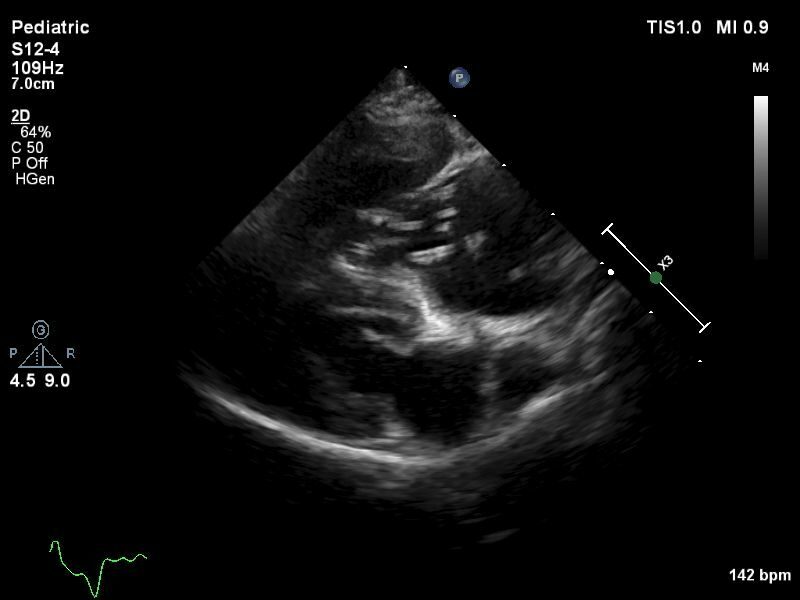

Die Diagnose wird meist nicht gestellt, weil ein Hund symptomatisch ist, sondern weil er aus einem endemischen Gebiet importiert wurde. Tatsächlich sind die meisten an uns überwiesenen Hunde asymptomatisch . Dann stellt sich die Frage, ob die Diagnose auch stimmt und ob entsprechend eine Behandlung indiziert ist. Gemäß der Empfehlung der American Heartworm Society (AHS) sollte die Diagnose basierend auf zwei positiven Testresultaten bestätigt sein. Das kann theoretisch ein Nachweis von Larven durch einen Knott’s Test plus ein positiver Antigentest sein. Nachdem ein Knott’s Test nicht als sensitiv gilt, führe ich diesen nie durch, sondern wiederhole bei einem überwiesenen Patienten zuerst einen Antigentest in einem anderen Labor. Teils können zwar Larven in einem Blutausstrich direkt unter dem Mikroskop gesehen werden; häufiger handelt es sich dabei aber um D. repens. Schließlich können in Einzelfällen adulte Würmer in der Lungenschlagader echographisch dargestellt werden, was dann als beweisend gilt.